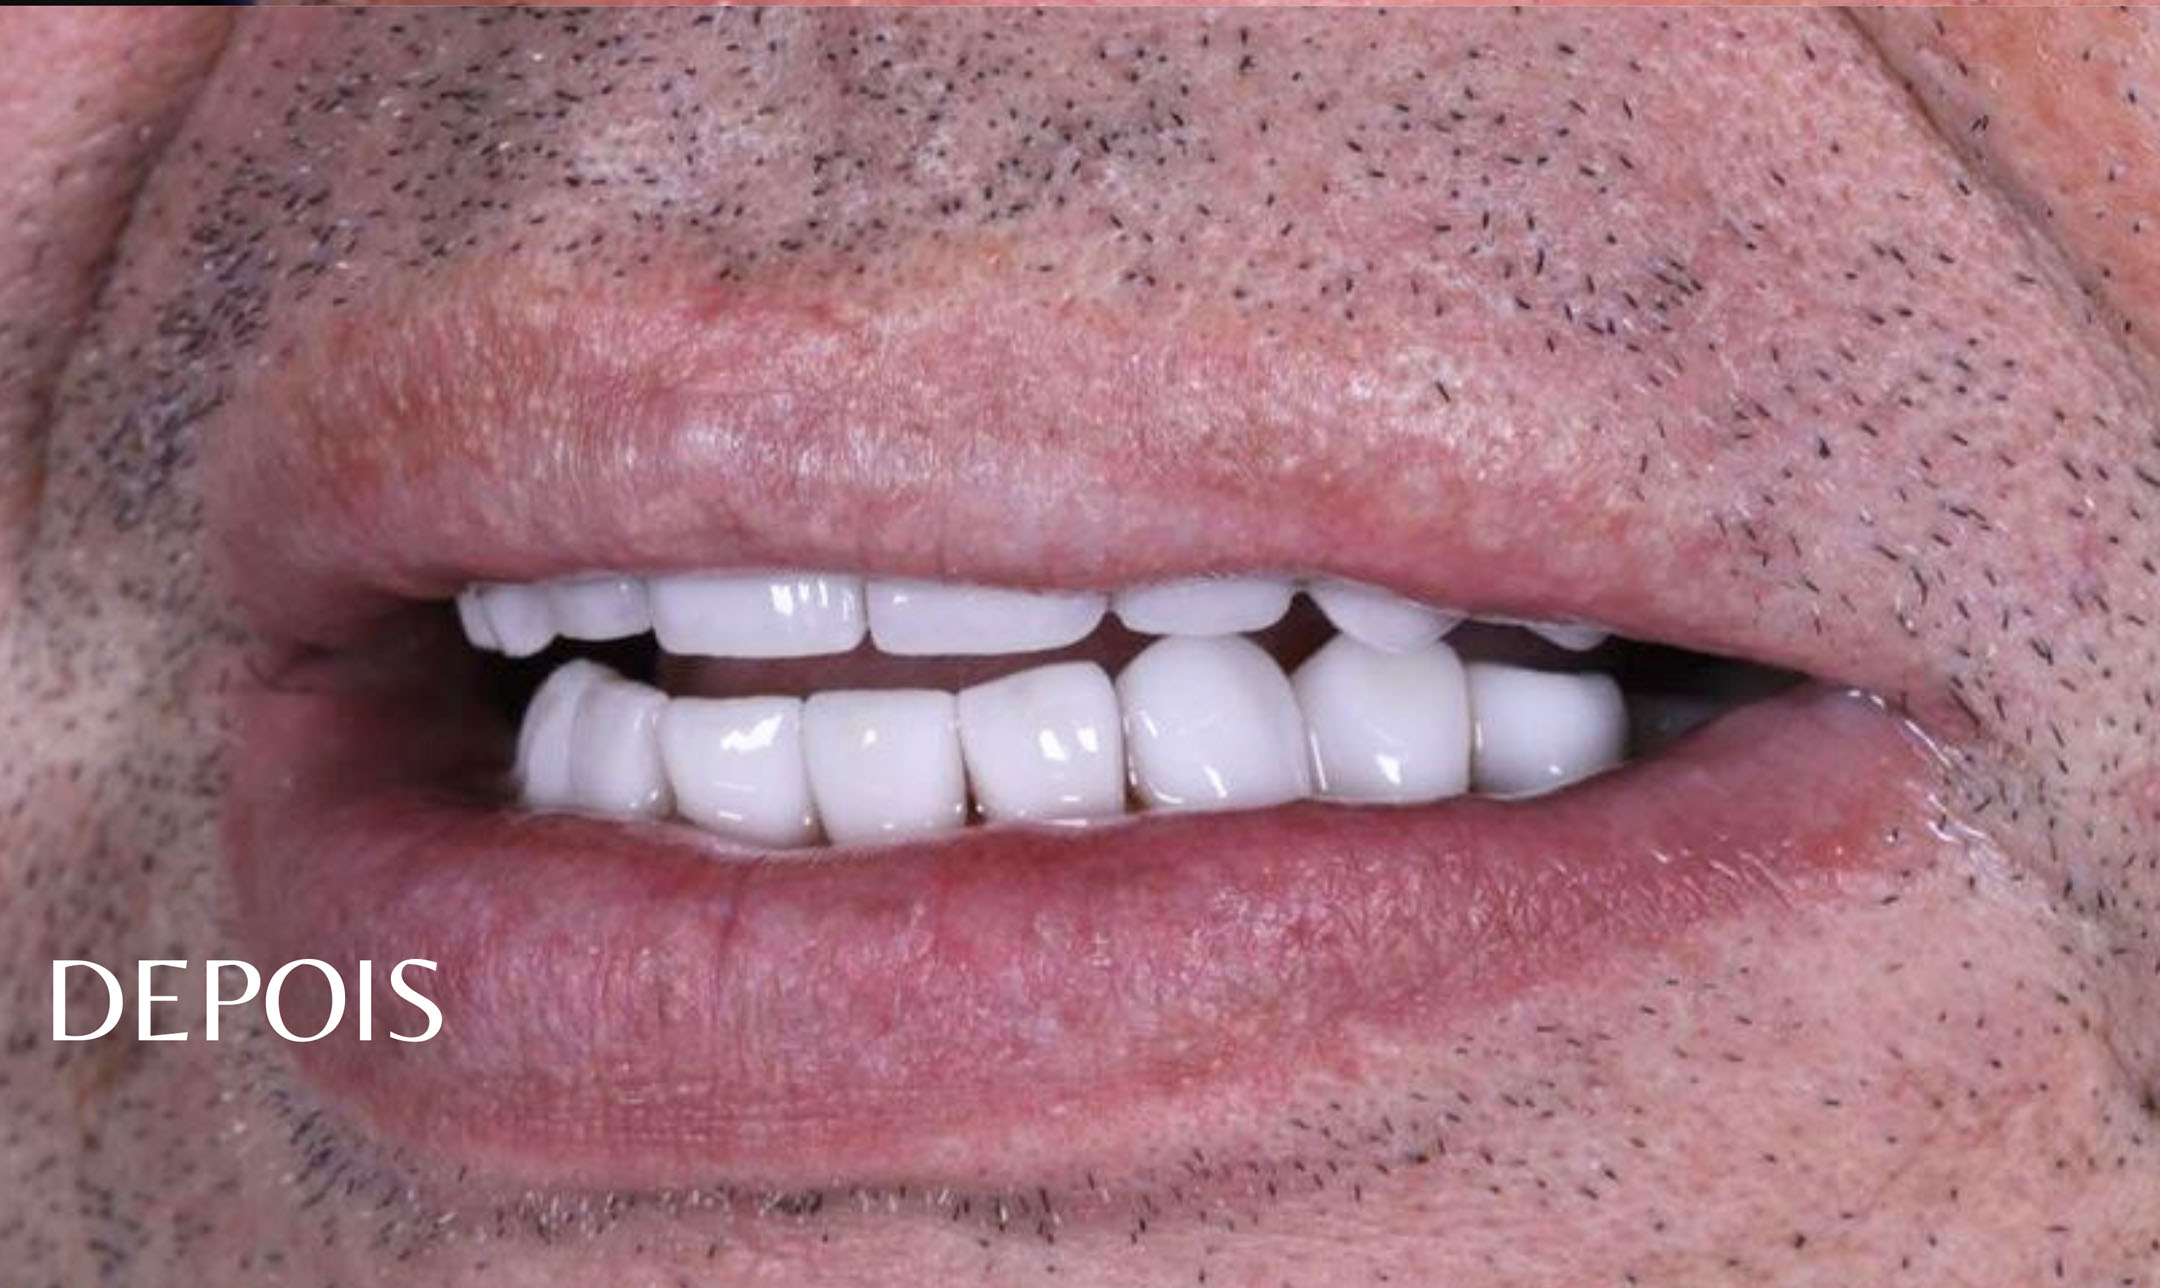

Indicada para situações de perda de todos os dentes, esta prótese reproduz completamente uma arcada dentária. Feita sob medida, é fixada sobre a gengiva. Além de melhorar a estética, a prótese total devolve todas as funções essenciais dos dentes ao paciente.

É uma prótese total fixada por pinos de implante, oferecendo uma solução definitiva para quem busca conforto e segurança ao falar, mastigar e sorrir.

Procedimento que melhora a aparência dos dentes e do sorriso, incluindo clareamento dental, facetas de porcelana e restaurações.

Ambas as opções são usadas para corrigir imperfeições como descoloração, desalinhamento e desgaste dental, proporcionando um sorriso mais harmonioso e atraente.

Cada pessoa tem suas particularidades e merecem um cuidado especial e personalizado para suas características, por isso, trabalhamos analisando cada caso, para que possamos entregar o resultado mais natural e bonito possível.